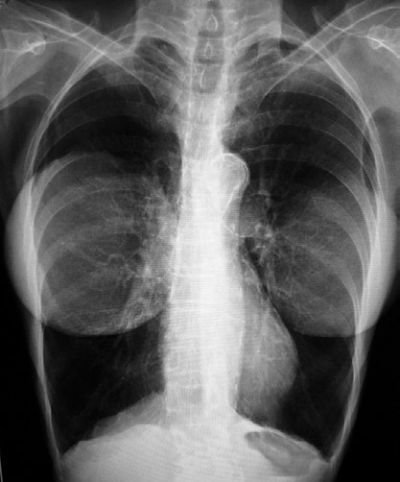

James Heilman / Wikimedia

Rentgenski snimak prsnog koša s obostranim implantatima u dojkama